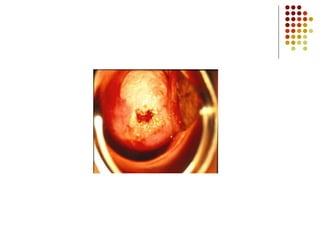

Ejemplos de Tumores

Pulmonar